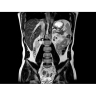

Пациентам с такими хроническими заболеваниями печени, как фиброз и цирроз, часто требуется регулярное наблюдение гастроэнтеролога. Это может потребовать проведения инвазивных процедур, которые не всегда позволяют получить полную информацию о состоянии печени.

Новая ИП MR-Touch, разработанная компанией GE совместно с клиникой Майо, основана на исследовании печени с помощью акустических волн, в ходе которого выявляются различия в жесткости тканей. Результатом исследования является эластограмма, полное изображение печени. По таким эластограммам радиологи и гастроэнтерологи могут периодически контролировать состояние пациента и принимать информированные решения о терапии. Более того, данная методика открывает новые возможности и позволяет оказывать инновационные услуги имеющимся пациентам и привлекать новых клиентов.